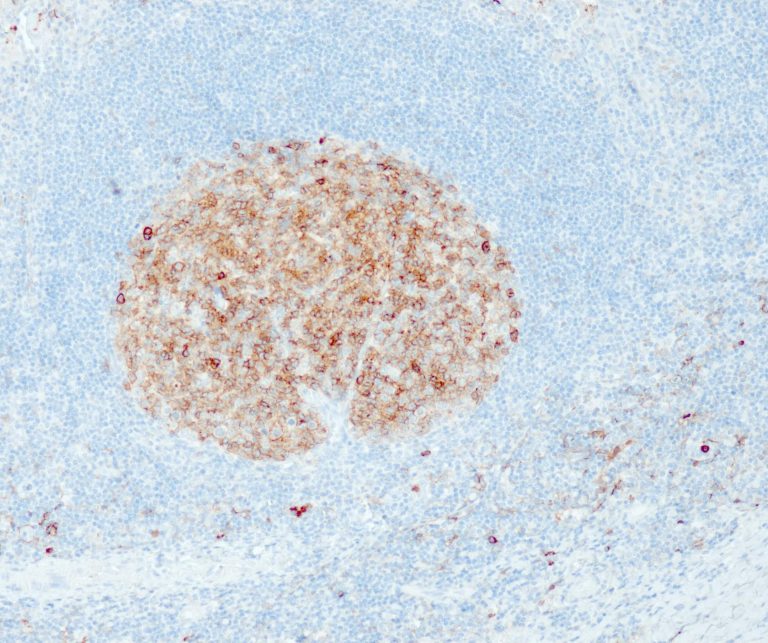

Vascular Pathology

Gastrointestinal (GI) Pathology

General Marker

Breast Pathology

Endocrine Pathology

Gynecological Pathology

Neuropathology

Infection Markers

Lung Pathology

Urinary Tract Pathology

Transplantation Pathology

Soft Tissue Pathology

Hematopathology